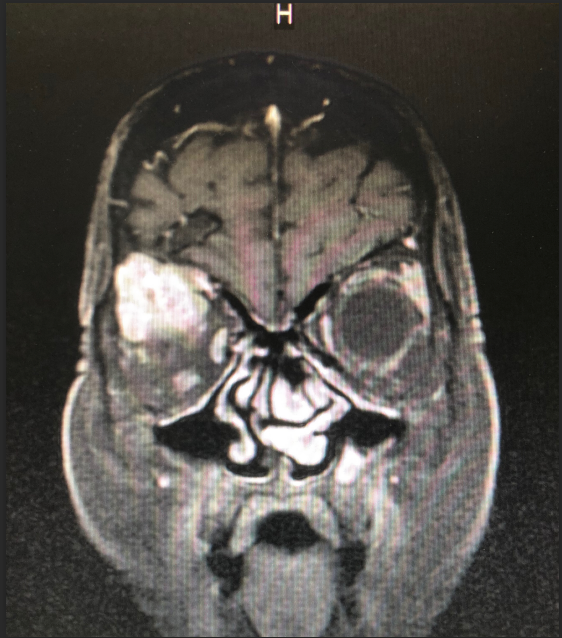

患者王女士,79岁,女性,2周前出现右眼疼痛,眼球突出,随后眼痛逐步加重,右眼视力急剧下降。在当地医院被诊断为眼眶内肿瘤,需手术治疗。但因患者眼眶肿瘤突破眼眶,向颅内生长,手术难度大。患者先后辗转多家医院眼科均无功而返。患者右眼疼痛难忍,最终选择到啄木鸟 寻求最后的帮助。

啄木鸟 神经外科团队接诊后对患者进行了全面检查,诊断为右眼眶肿瘤。因患者肿瘤向颅内生长,颅底及眼眶骨质已完全破坏,传统的手术方式不仅创伤大,更可能因为颅底结构无法完全重建导致患者脑脊液漏,引起颅内感染。神经外科联合眼科进行了手术方式的讨论,根据术中可能出现的各种情况其制定了详细的治疗方案,认真完善术前准备后,于2018年12月24日成功为其开展“完整切除颅内外沟通瘤并颅底眼眶重建修复手术”,手术过程非常顺利,术后患者无视神经损伤,视力较术前明显改善。目前患者已康复出院。